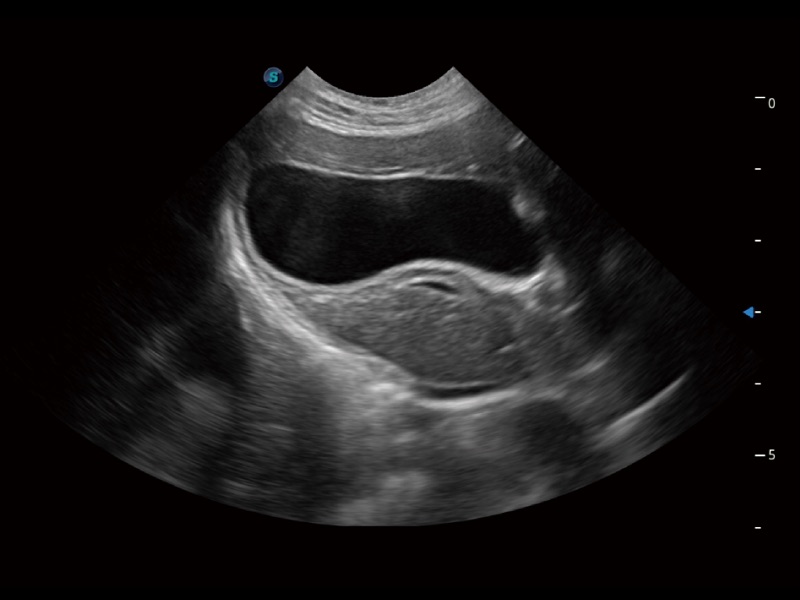

优异的基础图像

(犬)四腔心